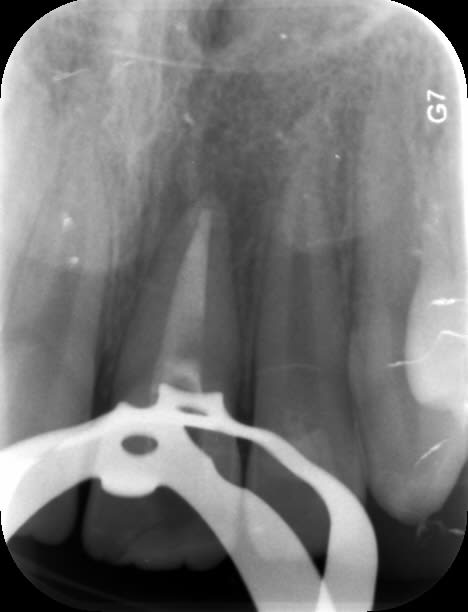

Enfant de 12 ans adressé par son dentiste le lendemain d'un trauma avec fracture de 21 et 22.

- 21 est une incisive mature mais jeune. Les cornes pulpaires sont très proéminentes et une fracture même d'apparence minime a donc une implication pulpaire directe. Il faut recouvrir en urgence le trait de fracture : ici par un CVIMAR (Fuji II LC). Une restauration par résine composite sera réalisée.

- 22 présente une exposition pulpaire ancienne de 20 heures. 20 heures donc que les germes buccaux contaminent directement la pulpe, heureusement jeune et donc avec un fort potentiel de défense.

Une pulpotomie partielle est réalisée afin d'éliminer le tissu le plus contaminé. De la Biodentine est utilisée ; son avantage par rapport au MTA est de ne pas noircir. Du CaOH aurait un taux de succès moindre.

Si le patient avait été vu le jour même du trauma, une exérèse pulpaire a minima (1 mm pour loger le matériau) aurait été suffisante.